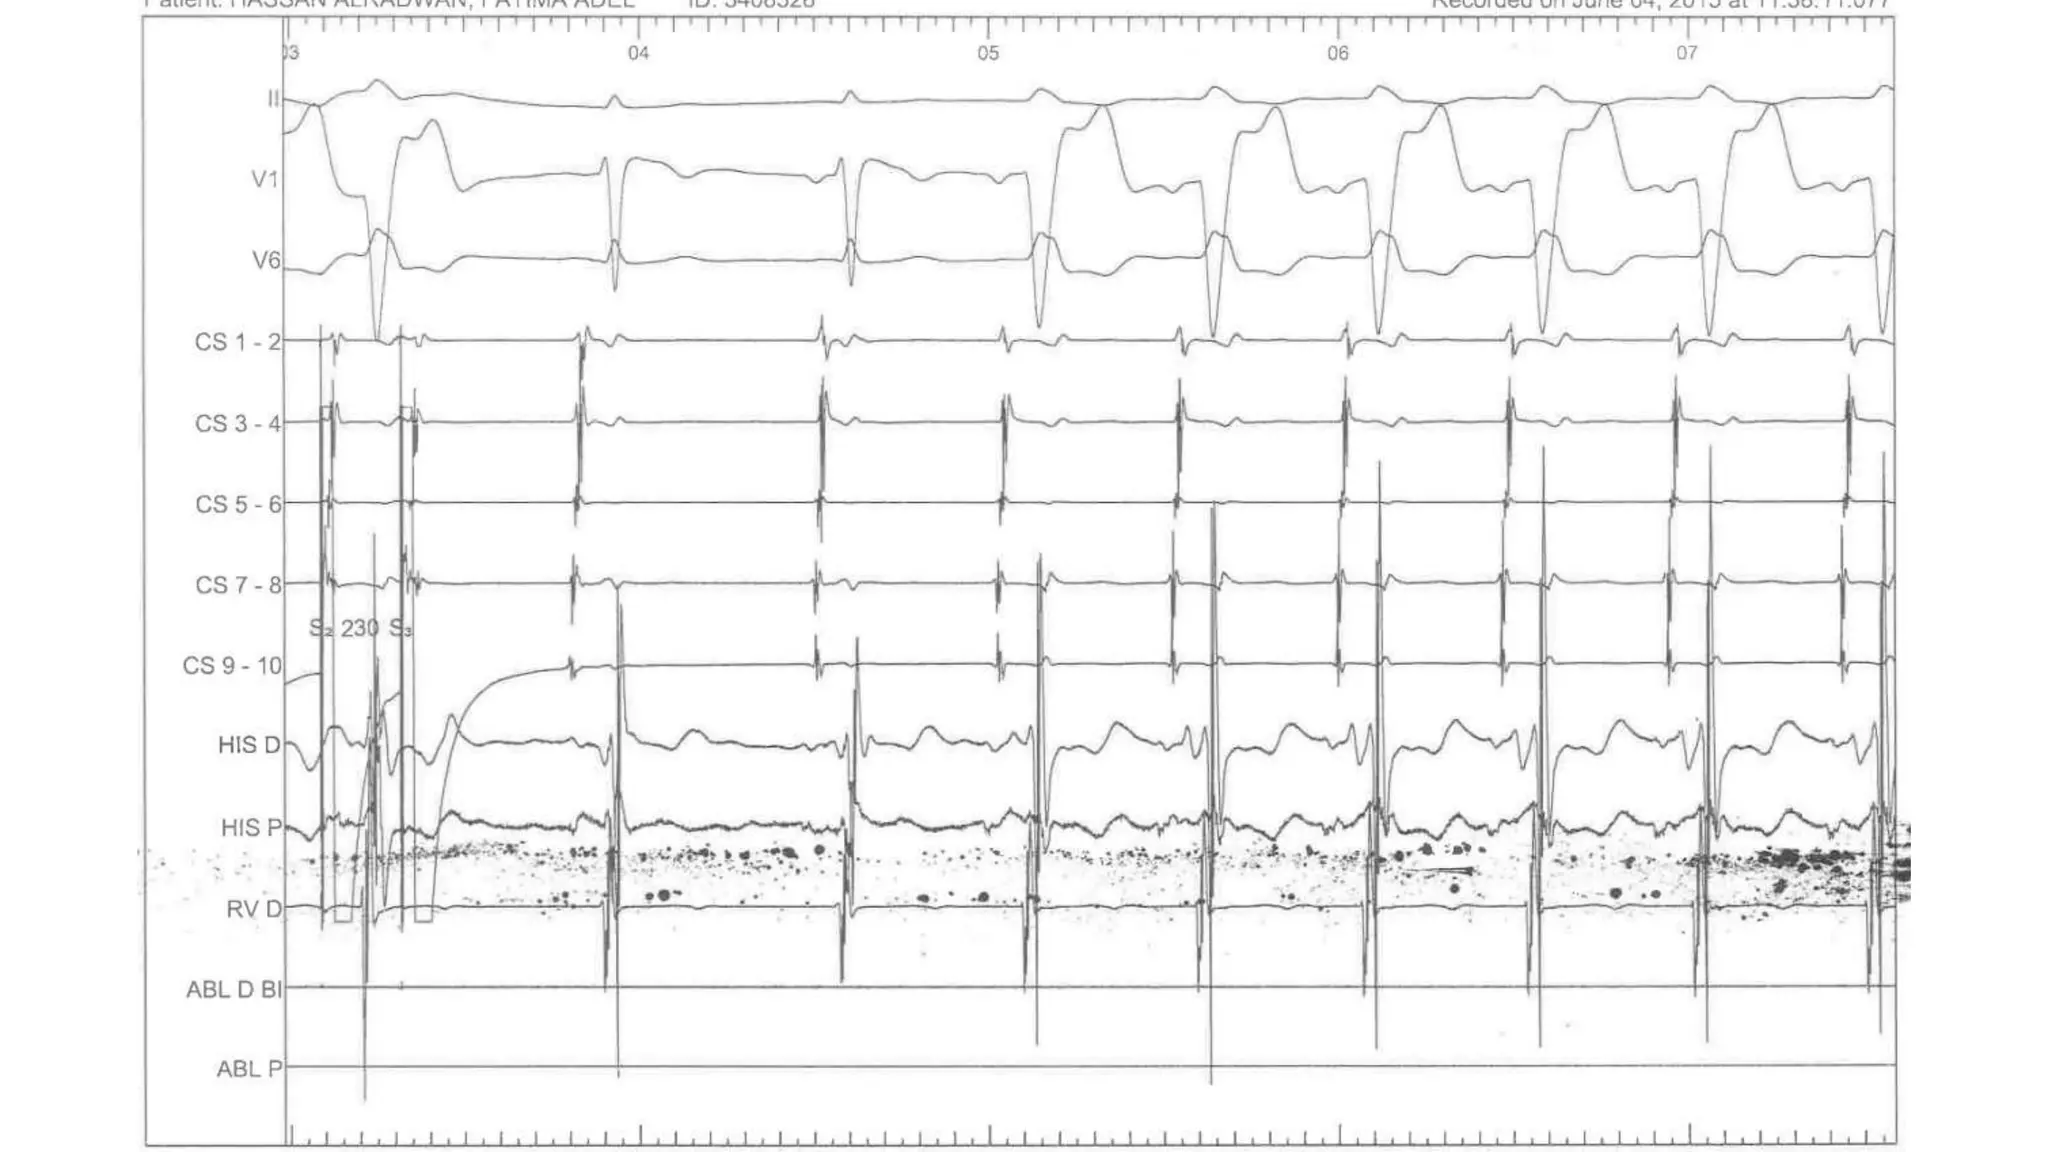

An electrophysiologic study involves inserting electrode catheters into the heart to record electrical activity and induce arrhythmias. The document discusses: 1. The procedure involves placing catheters in the heart to record electrograms from the atria, His bundle, ventricles and coronary sinus. 2. The aims are diagnostic to evaluate arrhythmias and bradycardias, and therapeutic for ablation of arrhythmias. 3. Key measurements taken include intervals between P waves, His bundle activation and QRS complex to identify conduction abnormalities. 4. Tracings are analyzed to determine the rhythm, sequence of activation, effects of pacing, and identify arrhythmia mechanisms like accessory pathways